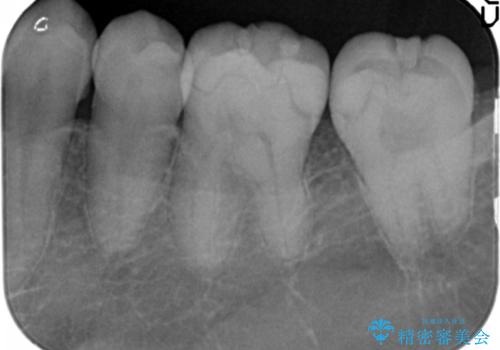

- 以前治療した歯の違和感、しみる感じの改善を求めて来院されました。

保険適応の素材、レジン素材による修復が行われていますが、X線写真より修復物の下には透過像(黒い影)が認められ、症状からも虫歯の再発が強く疑われます。